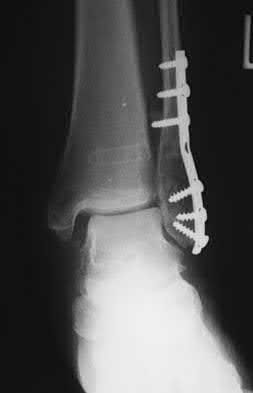

A 25-year-old female is involved in a motor vehicle collision. She presents with the isolated injury seen in Figures A through D. Her leg is swollen but her skin is intact. She has no clinical signs of compartment syndrome. Which of the following treatment options will allow for maintenance of fracture alignment and minimize the risk of soft tissue complications?

The patient presents with a closed distal third metaphyseal-diaphyseal distal tibia fracture with simple intra-articular extension. Immediate intramedullary nailing along with percutaneous fixation of the articular component provides appropriate restoration of length, rotation and alignment and minimizes the risk of wound complication.

Displaced distal third tibia fractures may be associated with simple intraarticular extension. Operative treatment of intra-articular distal tibia fractures has historically been performed with open reduction and internal fixation. Early open reduction and plate fixation of pilon fractures has been associated with high rates of infection and wound complication. In select patterns with simple articular extension, percutaneous screw fixation and medullary nailing may provide appropriate reduction with minimal soft-tissue risk.

Figures A and B demonstrate a distal third tibial shaft fracture with simple intra-articular extension. The axial and coronal CT cuts in Figures C and D further clarify the articular injury. Illustrations A and B demonstrate a comminuted distal third tibial fracture with simple intra-articular extension. Illustrations C and D are fluoroscopic images of the same injury after intramedullary nailing and percutaneous fixation of the articular component.